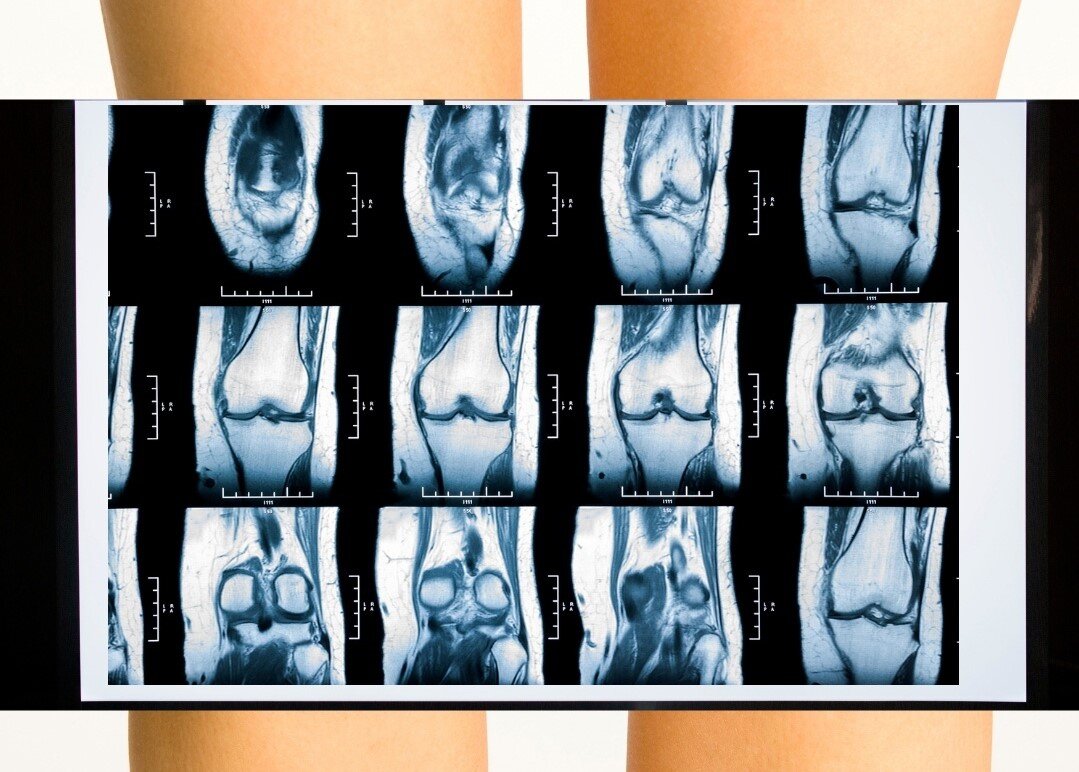

- X-ray of a finger.

The basic technique that allows you to determine the majority of fractures. Pictures are taken in two projections. On radiographs, a fracture line, the number and direction of displacement of fragments are visible. - CT finger. It is prescribed for insufficient information content of the baseline study. Allows you to get a three-dimensional image of the damaged phalanx, confirm the presence and clarify the location of the fracture.

- Finger MRI. It is required in doubtful cases in children of a younger age group and if a growth plate injury is suspected. Well visualizes cartilaginous tissue, which is practically not visible on conventional radiographs.